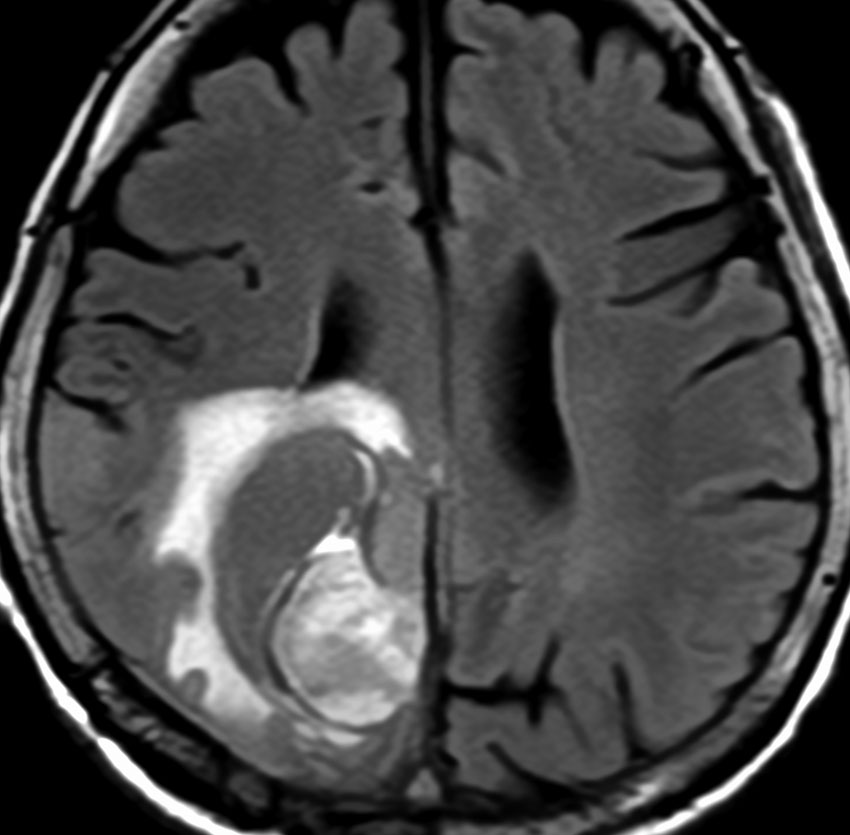

40代女性の後頭部傍矢状洞部の硬膜に発生したグレード3です。腫瘍周囲の強い浮腫のために,頭頂葉のゲルストマン症候で発症しました。術前診断は髄膜腫でしたが,腫瘍内部にのう胞(液体が溜まっている)があり,髄膜腫としては典型的な画像ではありません。右側の血管撮影にみられるように,上矢状洞が一部狭窄して腫瘍が浸潤している所見があり,腫瘍が濃染します。腫瘍の周囲の脳には出血がありました。大脳鎌と上矢状洞の壁を含めて全摘出しました。

画像と病理所見4

40代男性の大脳鎌テント接合部の硬膜に発生したグレード3です。激しい出血のために腫瘍摘出を部分摘出で中断せざるを得なかった例です。

この例でも,硬膜発生腫瘍ということは手術前の画像診断で解ってはいたのですが,髄膜腫と異なり不整な形をしてのう胞があり,一部は腫瘍壊死でした。

上の2例は,髄膜腫とは違うと一見してわかる,典型的なSFT/ヘマンジオペリサイトーマの例ですが,髄膜腫と鑑別できないようなものの方が多いです。